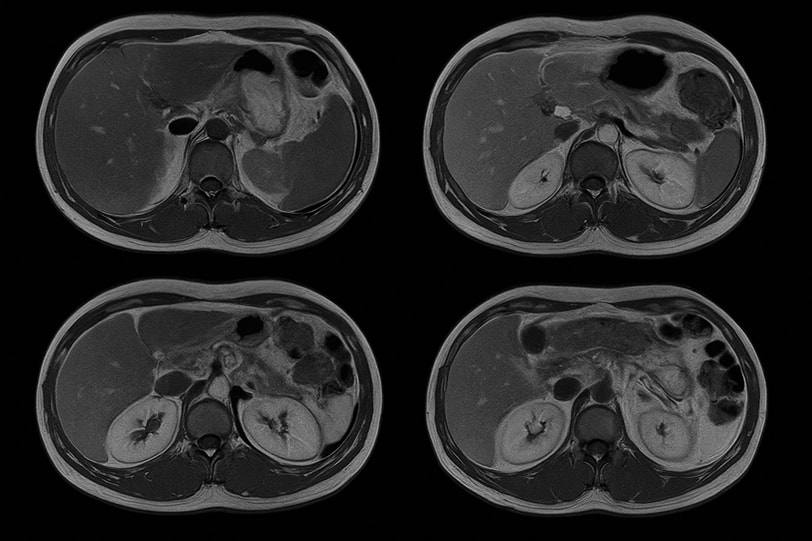

МРТ забрюшинного пространства с контрастом — информативный метод диагностики, позволяющий подробно рассмотреть внутренние органы и ткани, расположенные за брюшиной. После введения препарата врач получает четкие снимки, на которых видны мельчайшие сосуды и изменения структуры тканей.

Исследование помогает выявить воспаления, кисты, опухоли, аневризмы, последствия травм. При контрастном усилении становится заметна граница между здоровыми и измененными участками. Особенно ценно такое обследование при подозрении на патологии почек, надпочечников и поджелудочной железы.

Сначала выполняется серия снимков без контраста, затем вводится препарат, усиливающий контрастность тканей. После этого делают вторую серию сканирования.

Магнитно-резонансная томография с контрастированием позволяет врачу рассмотреть сосуды, мягкие структуры и лимфатические узлы. Во время обследования пациент не испытывает боли. В среднем процедура занимает около 30–40 минут, после чего можно сразу вернуться к обычным делам.

После магнитно-резонансной томографии с контрастным веществом врач анализирует изображения. В заключении указываются форма и структура органов, характер накопления контраста, состояние сосудов и лимфоузлов.

МРТ забрюшинного пространства с контрастированием помогает отличить воспаление от опухоли и определить границы патологического процесса. Результаты доступны в день обращения. Пациент получает отчет и диск с изображениями.